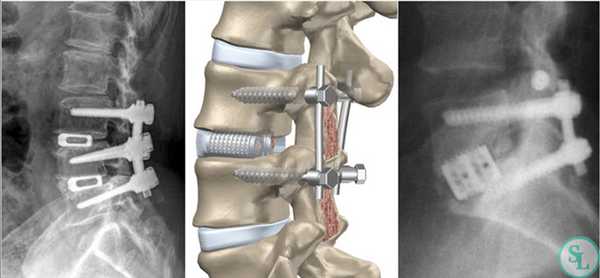

Декомпрессивно-стабилизирующая хирургия

Декомпрессивные операции иногда сочетаются с имплантацией стабилизирующей системы, если есть необходимость устранения или предупреждения нестабильности позвонков. Фиксация (стабилизация) после освобождения нервно-сосудистых образований подразумевает скрепление предрасположенных к анормальному смещению позвонков специальными конструкциями и имплантатами неподвижного или динамического типа.

Неподвижная тактика соединения - это укладка в межпозвонковое отверстие костного трансплантата или кейджа для обездвиживания и формирования спондилодеза (сращения) двух и более позвонков с последующей фиксацией стабилизированного участка титановой металлоконструкцией. Костный материал для пересадки обычно берется у пациента из гребня повздовшной кости, реже применяют аллотрансплантаты.

Динамическая стабилизация - имплантация протезных устройств, которые надежно стабилизируют патологическую зону, но не блокируют полностью подвижность между телами позвонков. Диапазон движений не будет выходить за порог физиологически допустимых значений.

На шейных уровнях применяются и стабилизирующие тактики оперативных вмешательств, каждая из которых, кстати, может идти совместно и с другими видами операций. Наиболее популярные из стабилизирующих методов:

Если клиника симптомов не поддается консервативной терапии или неинвазивные способы не могут быть задействованными ввиду сильно прогрессирующего стеноза, назначается операция. Вмешательство предполагает использование декомпрессионной ламинэктомии под общим наркозом. При комбинированной проблеме, например, вместе с грыжей, ее сочетают с микродискэктомией и спондилодезом. При спондилодезе осуществляют скрепление смежных позвонков металлическими фиксаторами (стержнями, пластинами, крючками и пр.), установку межтеловых имплантатов или вживление костного трансплантата с металлической гильзой.

Установка металлической конструкции.

Декомпрессивно-стабилизирующая операция

Часто возникает необходимость сочетать декомпрессионные хирургические вмешательства с установкой стабилизирующей позвонки системы. Это является надежным залогом устранения риска возникновения или уже существующей нестабильности позвонков.

Стабилизирующие операции выполняют вторым этапом после устранения давления на нервно-сосудистые образования. Они заключаются в соединении склонных к смещению позвонков между собой специальными конструкциями жесткой или динамической фиксации, что невозможно эндоскопическим путем. Поэтому при возникновении необходимости в установке стабилизирующей системы декомпрессию позвоночника выполняют посредством операций с микроскопом.

Жесткие стабилизирующие системы

Системы жесткой фиксации подразумевают установку в межпозвонковое пространство костного трансплантата (обычно взятого из подвздошной кости пациента) или специального искусственного кейджа с последующим монтажом на два и более соседних позвонка металлической конструкции. В результате они обездвиживаются и со временем сращиваются между собой, т. е. происходит спондилодез.

Метод позволяет полностью устранить сегментарную нестабильность позвоночника, но при необходимости фиксации одновременно большого количества позвонков провоцирует уменьшение возможной амплитуды движений.

Жесткая стабилизация подразумевает использование техники транспедикулярной фиксации или транскутанной стабилизации. Они очень похожи между собой и отличаются одинаковой эффективностью, но последняя обладает лучшим косметическим эффектом, поскольку все манипуляции осуществляются через точечные проколы мягких тканей.

Суть метода состоит в применении специальных титановых винтов и пластин. Винты вкручиваются в точку пересечения поперечных отростков позвонка с суставными по обеим сторонам позвонка. Таким образом, фиксируется минимум 2 позвонка, хотя в ряде ситуаций требуется стабилизация значительного большего количества позвоночно-двигательных сегментов. Через шляпки винтов пропускают титановую пластину, обеспечивающую жесткость конструкции и распределение нагрузки на нее.